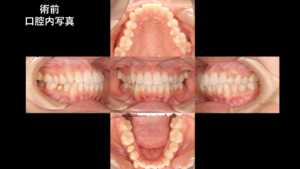

患者さん:20代女性

主訴:出っ歯が気になる/上の奥歯の痛み

今回の症例は、単純な出っ歯ではなく、埋伏犬歯+乳歯残存+破折歯といった複合的な問題を伴っていました。

前歯の突出感が改善し、歯列全体のバランスが整いました。また、それにより、咬合が安定しています。